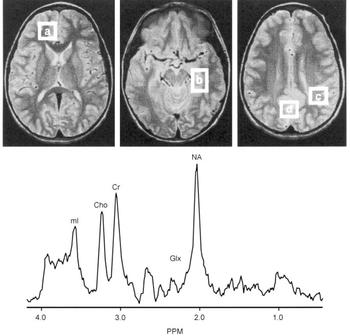

Proton magnetic resonance spectroscopy (MRS) spectra were acquired from 8cc regions of interest (ROIs) in the frontal, temporal, parietal and occipital lobes, with an acquisition time of 5 min/ROI (STEAM pulse sequence TE 30 ms, TM 13.7 ms, TR 2000 ms (Reference Frahm, Merboldt and HanickeFrahm et al, 1987) Fig. 2). Using proton MRS, we have been able to quantitate regional brain mI concentrations with excellent reliability (Reference Moore, Bebchuk and ParrishMoore et al, 1999). Using a test—retest design (scan interval range 1-12 weeks) in six healthy volunteer subjects, the brain mI concentration (expressed in units of mI × 104/brain water and reported as the mean (standard error)) was 2.57 (0.28) v. 2.50 (0.24) with a mean difference of 0.07 or ±3% of the mI measure, demonstrating that the temporal stability and test—retest reliability of this measure are remarkably good. In order to evaluate the interrater reliability of this method, two trained individuals analysed the in vivo magnetic resonance data with MRUI-VARPRO time domain spectral analysis software (Reference Van den Boogaart, Ala-Korpela and JokisaariVan den Boogaart et al, 1994; Reference de Beer, van den Boogaart and van Ormondtde Beer et al, 1992). The individuals were masked to the study information and to each other's results. Intraclass correlation coefficient analysis revealed an interrater reliability of more than 98%.

Fig. 2 Brain regions examined and typical proton magnetic resonance spectrum (MRS). Regions of interest: (a) frontal lobe, (b) temporal lobe, (c) parietal lobe, (d) occipital lobe. Lower panes: frontal lobe proton MRS from a bipolar disorder patient. PPM, parts per million, ml, myo-inositol; cho, choline compounds; Cr, creatine compounds; Glx, glutamate/glutamine/GABA; NA, N-acetyl compounds.